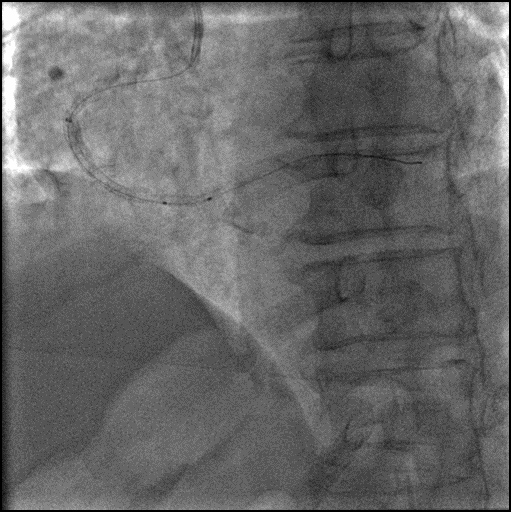

6F Telescope™ 导引延长导管加强支撑。

2.5x12mm NC, 3.0x15mm NC球囊反复高压扩张。

2.5x30mm Integrity Stent, 2.75x38mm Stent。

2.75x12mm NC, 3.0x15mm NC后扩张。

Final Result